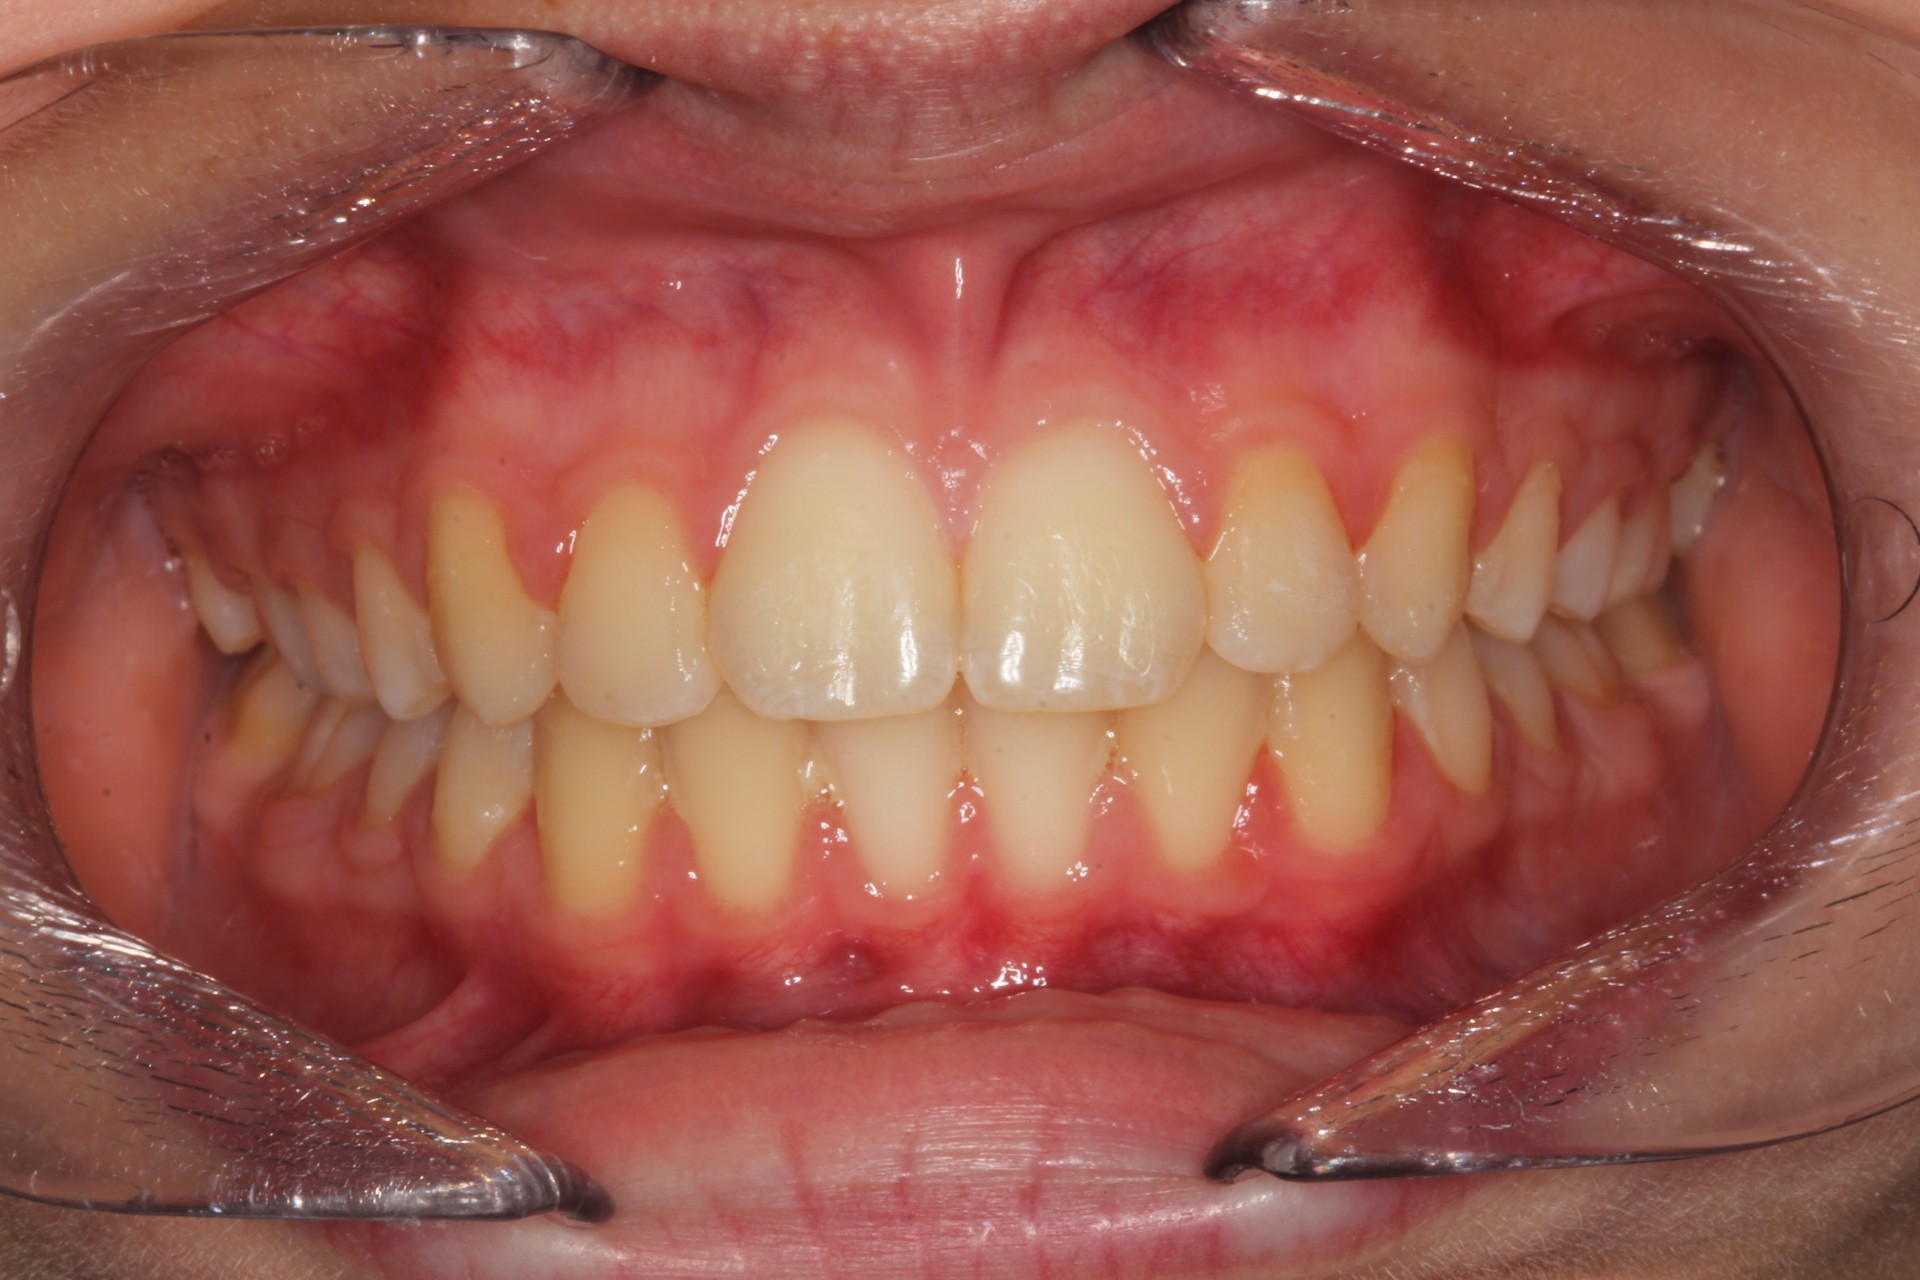

Protruding front teeth – Child case